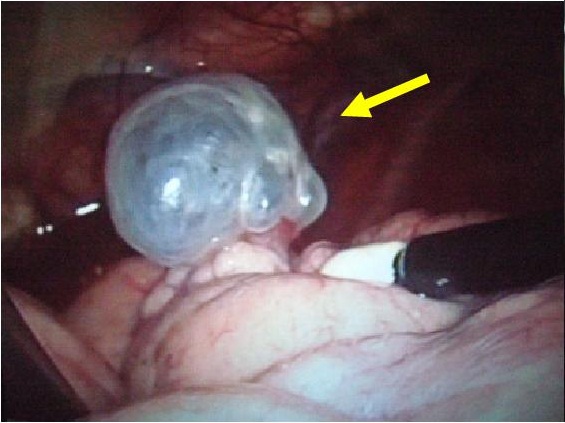

自然気胸の術中所見

肺嚢胞の結紮

肺嚢胞